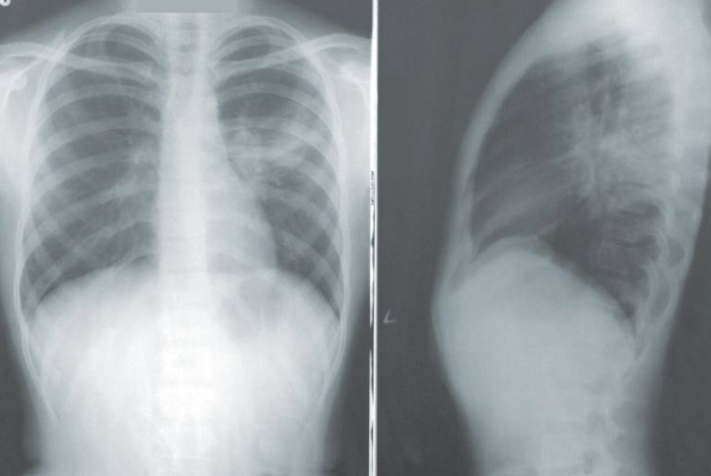

研究主要作者罗伯特·福图纳(Robert Fortuna)教授带领跨学科团队,于2022年1月启动协调计划,整合初级保健医生、放射科医生及胸外科医生资源。通过在电子健康记录中开发自定义算法,精准计算患者吸烟史并标记符合条件者,使筛查率从2022年3月的33%跃升至2025年6月的72%。数据显示,2023年至2024年期间,该项目诊断的63例肺癌病例中,近78%为早期发现,显著提高了治疗成功率。团队成员M. Patricia Rivera指出,肺癌筛查需量化吸烟史,这一复杂性导致识别符合条件者存在障碍,而算法的应用有效简化了流程。